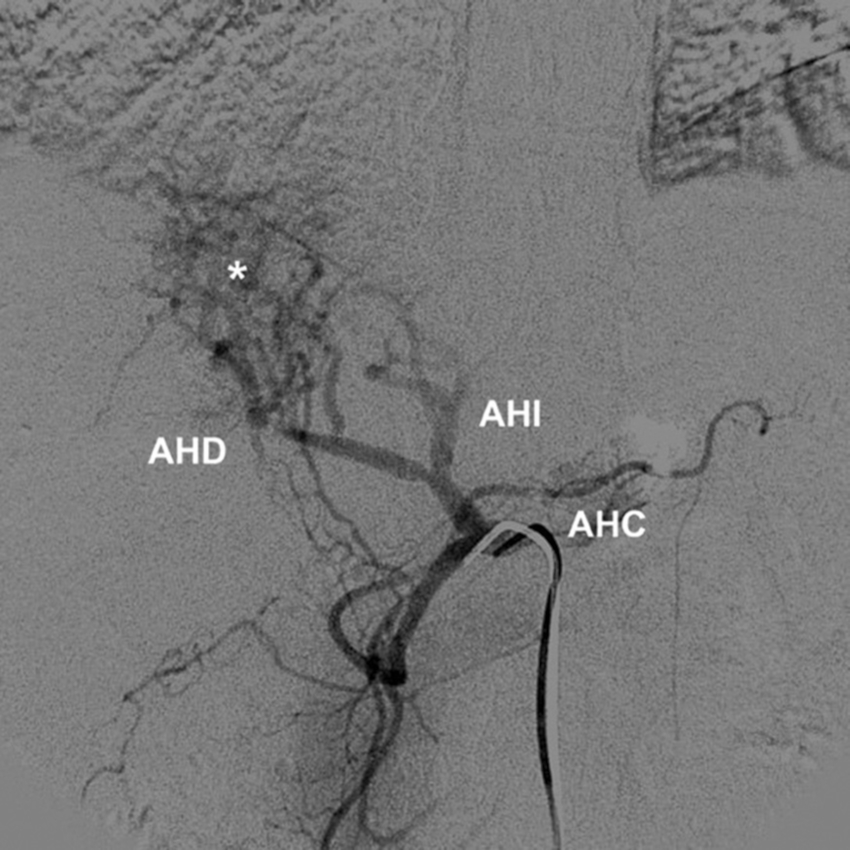

Tipo 8: AHD aberrante y AHI accesoria, o AHD accesoria y AHI aberrante (Figs. 15 y 16).

Tipo 9: la AHC emerge de la AMS (Fig. 17).